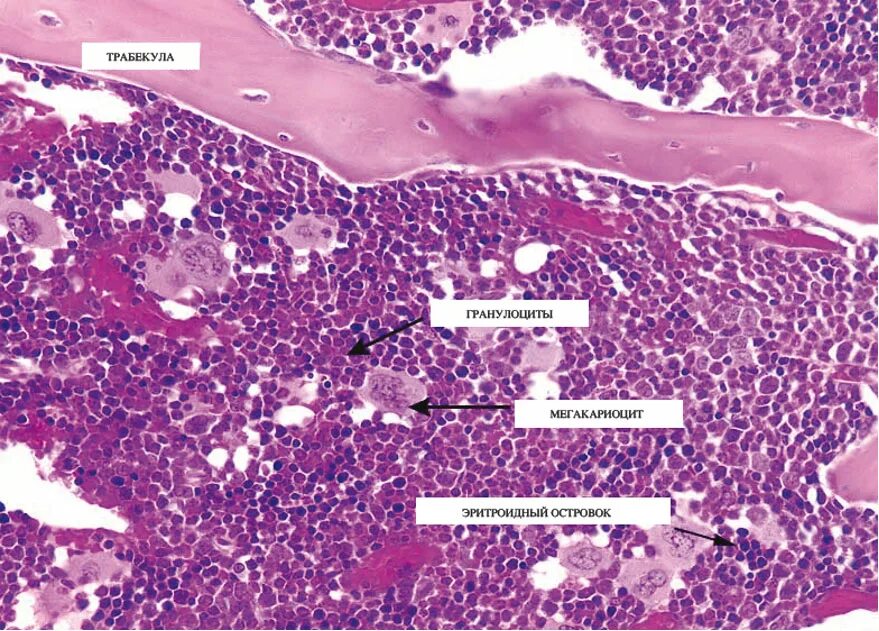

Гистология стромы что это